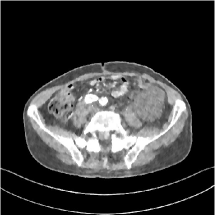

III.C.3. Analysis of Residual Maps

Here, we investigate the residual images over the layers of the MARS7 model. Fig. 12 displays the image reconstructed with MARS7 along with the residual images in different layers. The residual images are generated by applying the restoring operation to the corresponding columns of each residual matrix , forming images . Essentially, all the columns of are transformed into patches and accumulated back in the image to form the residual image in the th layer. We can observe that the residual images in the first three layers contain explicit structural information and we still find some delicate details in the fourth and fifth layers. However, we hardly see any valuable features in the residual images for the following layers, which is consistent with the fact that the transform is overwhelmed by noise in quite deep layers. Therefore, the ceiling for the potential of multi-layer sparsifying transform model may be 5 or 7 layers. The quantitive result also implies the same conclusion.